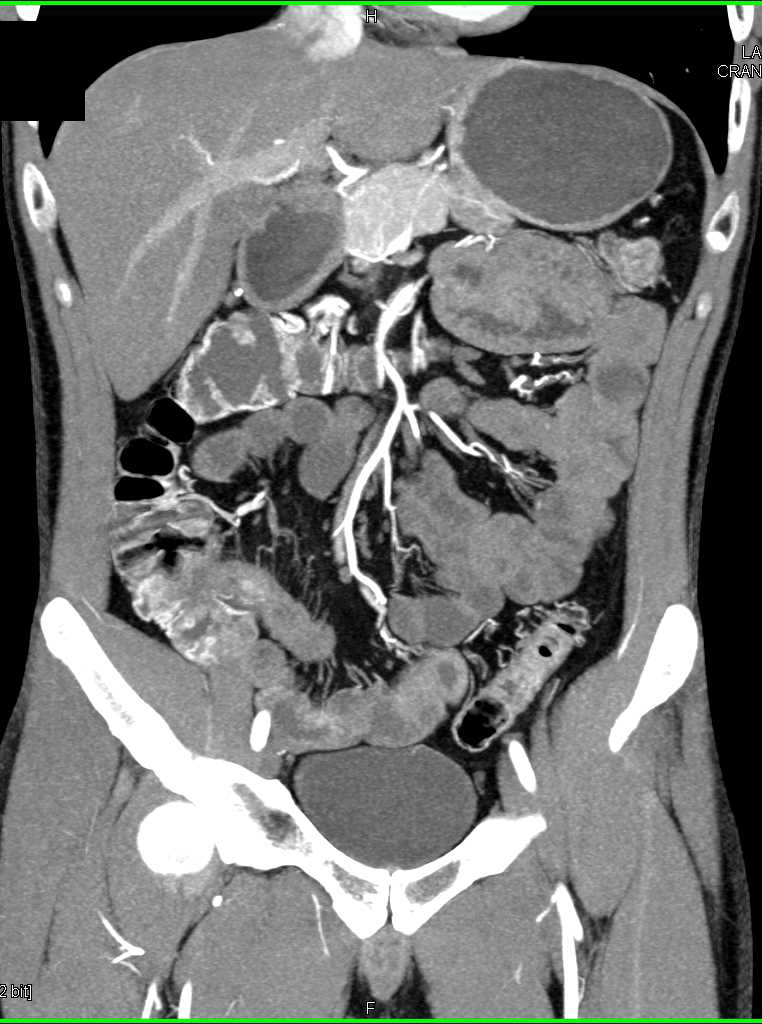

Fistulae from Colon to Abdominal Wall